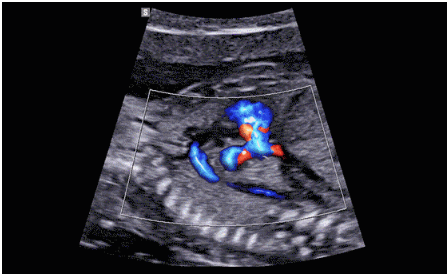

CrystalLive?是三星最新的超聲成像引擎,同時增強了2D圖像處理能力、3D渲染能力和彩色信號處理能力,能夠在復雜情況下提供出色的圖像性能,具備檢測外周血管、微循環(huán)血流的能力。